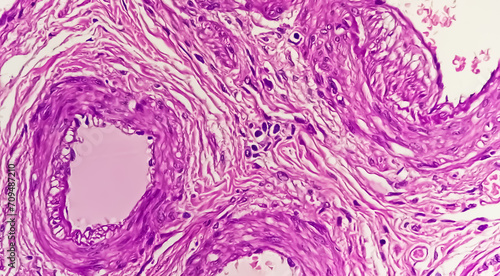

Mikrofotografi - Plakater, Poster, Billeder på lærred